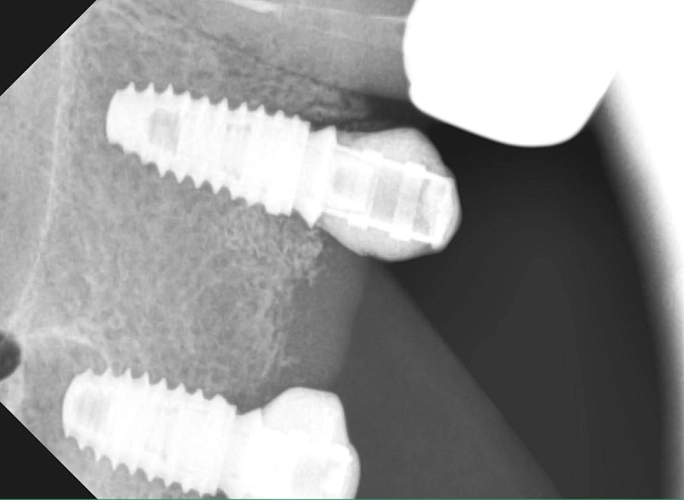

На фото клинический случай

В данном клиническом случае была проведена установка двух имплантов с целью восстановления трех зубов. На индивидуальных формирователях была сформирована десна, что обеспечило оптимальную эстетику и функциональность. Далее, на индивидуальных аббатментах, было выполнено протезирование с использованием циркониевых коронок.

Работа выполнена Федотовым Русланом Валерьевичем и врачом-ортопедом Винокур Анастасией Александровной.